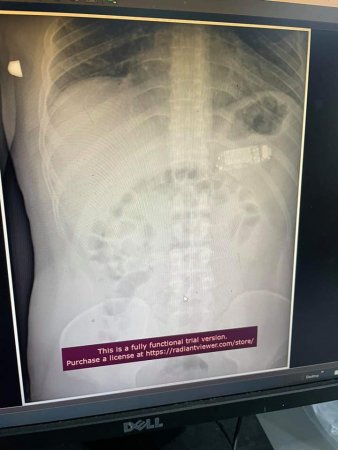

До лікарні за допомогою звернувся 33-річний місцевий житель, який проковтнув мобільний телефон Nokia 3310 цілком. З телефоном в шлунку він проходив чотири дні й тільки після цього звернувся до медиків. Чоловікові зробили рентген і на знімку дійсно виявили мобільний телефон з кнопками.

Хірургам довелося провести складну операцію і розділити телефон на три частини за допомогою ендоскопії. Сторонній предмет був занадто великим, щоб шлунок міг його переварити. Тим більше пацієнт був в небезпеці – акумуляторна кислота могла витекти та спровокувати сильне отруєння.

Варто відзначити, що хірурги впоралися з операцією без розрізання шлунка. Всі частини телефону дістали за допомогою ендоскопа. Операція пройшла успішно, без ускладнень і пацієнт відчуває себе добре. З якою метою він проковтнув мобільний телефон – він лікарям не розповів.